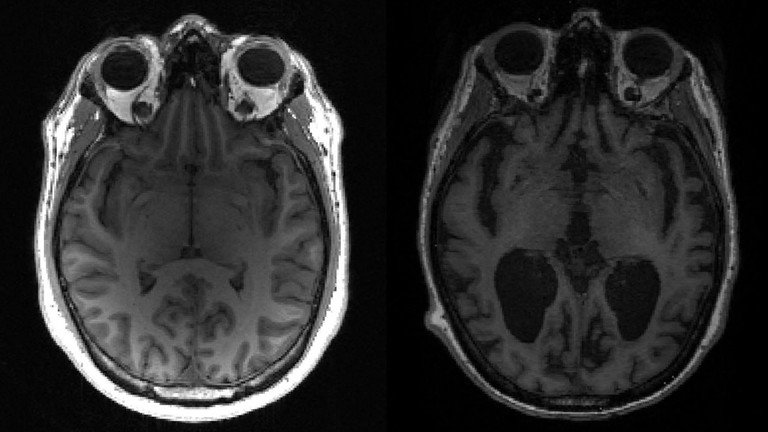

Bất ngờ xuất hiện căn bệnh thần kinh kỳ lạ ở Canada, người trẻ dễ mắc hơn hẳn. Các nhà chức trách cho biết, khoảng 150 thanh niên ở New Brunswick, Canada xuất hiện triệu chứng của một căn bệnh kỳ lạ gây ảnh hưởng đến não.

Căn bệnh kỳ lạ gây ảnh hưởng tới não. Ảnh: AFP

Nguồn tin từ Tổ chức Vitalité Health Network ở New Brunswick chia sẻ với tờ The Guardian rằng các triệu chứng của bệnh bao gồm ảo giác, khó suy nghĩ, hạn chế vận động, mất ngủ và sụt cân nhanh chóng. Chính quyền địa phương cho biết căn bệnh này không phải Alzheimer hoặc các bệnh thần kinh phổ biến khác.

Một số người đã so sánh căn bệnh này với bệnh Creutzfeldt-Jakob, một căn bệnh về não gây ra bởi các protein dị dạng được gọi là prion có thể dẫn đến tử vong, tuy nhiên các quan chức y tế vẫn chưa đưa ra kết luận.